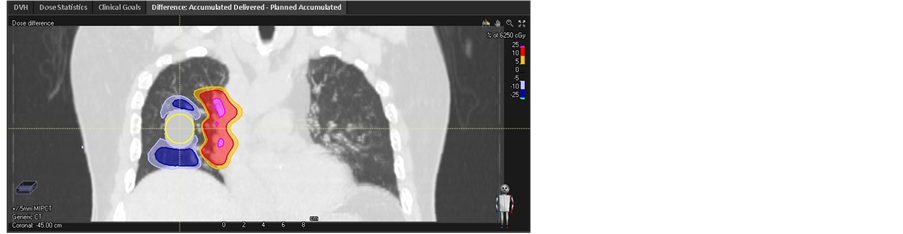

Each phase dose distribution was acquired using the plan had been implemented on the designing CT set respectively. Figure 3 demonstrates the dose volume histogram (DVH) of GTV for each phase and initial plan. In the case of MIP CT and CTavg_only based planning, the dispersion of GTV’s DVH is significantly larger comparing to the CTavg_tumor and CTavg_muscle based planning strategies which indicates lower dose delivered to target overall treatment due to using the inappropriate CT average image sets. The minimum of D98 for GTV reach 55.14 Gy in phase 5 mm and 47.51 Gy in phase 5 mm in the plan based MIP CT with initial GTV D98 = 60.09 Gy and CTavg_ only with initial GTV D98 = 60.10 Gy respectively. The dose difference on GTV was shown in Figure 4. While the worst case of D98 for GTV in the plan based CTavg_ tumor with initial GTV D98 = 60.07 Gy and CTavg_muscle with initial GTV D98 = 60.4 Gy are 58.29 Gy and 59.31 Gy respectively. CTavg_muscle shows slightly better coverage in the worst-case breathing phase image set. Table 1 lists the detail result.

The accumulative dose was calculated by sum up total phase dose distribution using the corresponding DVF. The dose difference and DVH between accumulative dose and planned dose on target were shown in Figure 5. In fact, the D98 of cumulative dose for GTV based CTavg_only and MIP CT are 53.48 Gy and 57.68 Gy, the corresponding discrepancy compared to planned dose reach to −11% and −4% respectively. While the D98 of cumulative dose for GTV based CTavg_muscle and CTavg_tumor are acquired as 60.19 Gy with discrepancy 0% and 59.73 Gy with discrepancy −1%, which is close to the initial plan dose. The dose discrepancy on GTV between cumulative dose and initial dose are larger for MIP CT and CTavg_only sensitivity of proton range and motion of the tumor uncertainties. While the corresponding discrepancy are relatively small for CTavg_muscle and CTavg_tumor, which is the reason that the proton plan was often implemented on CTavg_muscle or CTavg_tumor in most of the proton clinic.

As far as heart, the D1 are 1.88 Gy, 2.69 Gy, 3.74 Gy and 4.38 Gy in the initial plan based on MIP CT, CTavg_only, CTavg_tumor and CTavg_muscle respectively. But the D1 for heart reaches to 8.02 Gy on phase −5 mm on CTavg_tumor based plan, while the one is 10.21 Gy on phase −5 mm on CTavg_muscle based plan. The worst case dose difference in heart for plan based on CTavg_tumor and CTavg_muscle were shown in Figure 4. The accumulative dose through breathing phases are 8.07 Gy (+6.19 Gy), 2.96 Gy (+0.27 Gy), 5.98 Gy (+2.24 Gy) and 7.82 Gy (+3.44 Gy) for initial plan based on

Figure 4. Dose difference (a) between initial plan based CTavg_tumor and on phase −5 mm for heart, (b) between initial plan based CTavg_muscle and phase −5 mm for heart, (c) between initial plan based CTavg_only and phase 5 mm for target, (d) between initial plan based MIP CT and phase 5 mm for target.

MIP CT, CTavg_only, CTavg_tumor and CTavg_muscle respectively (compared to the initial plan). The results indicate that overriding ITV density could improve the target coverage. However, as a tradeoff, proton dose might stop into the heart at the distal end of the target.